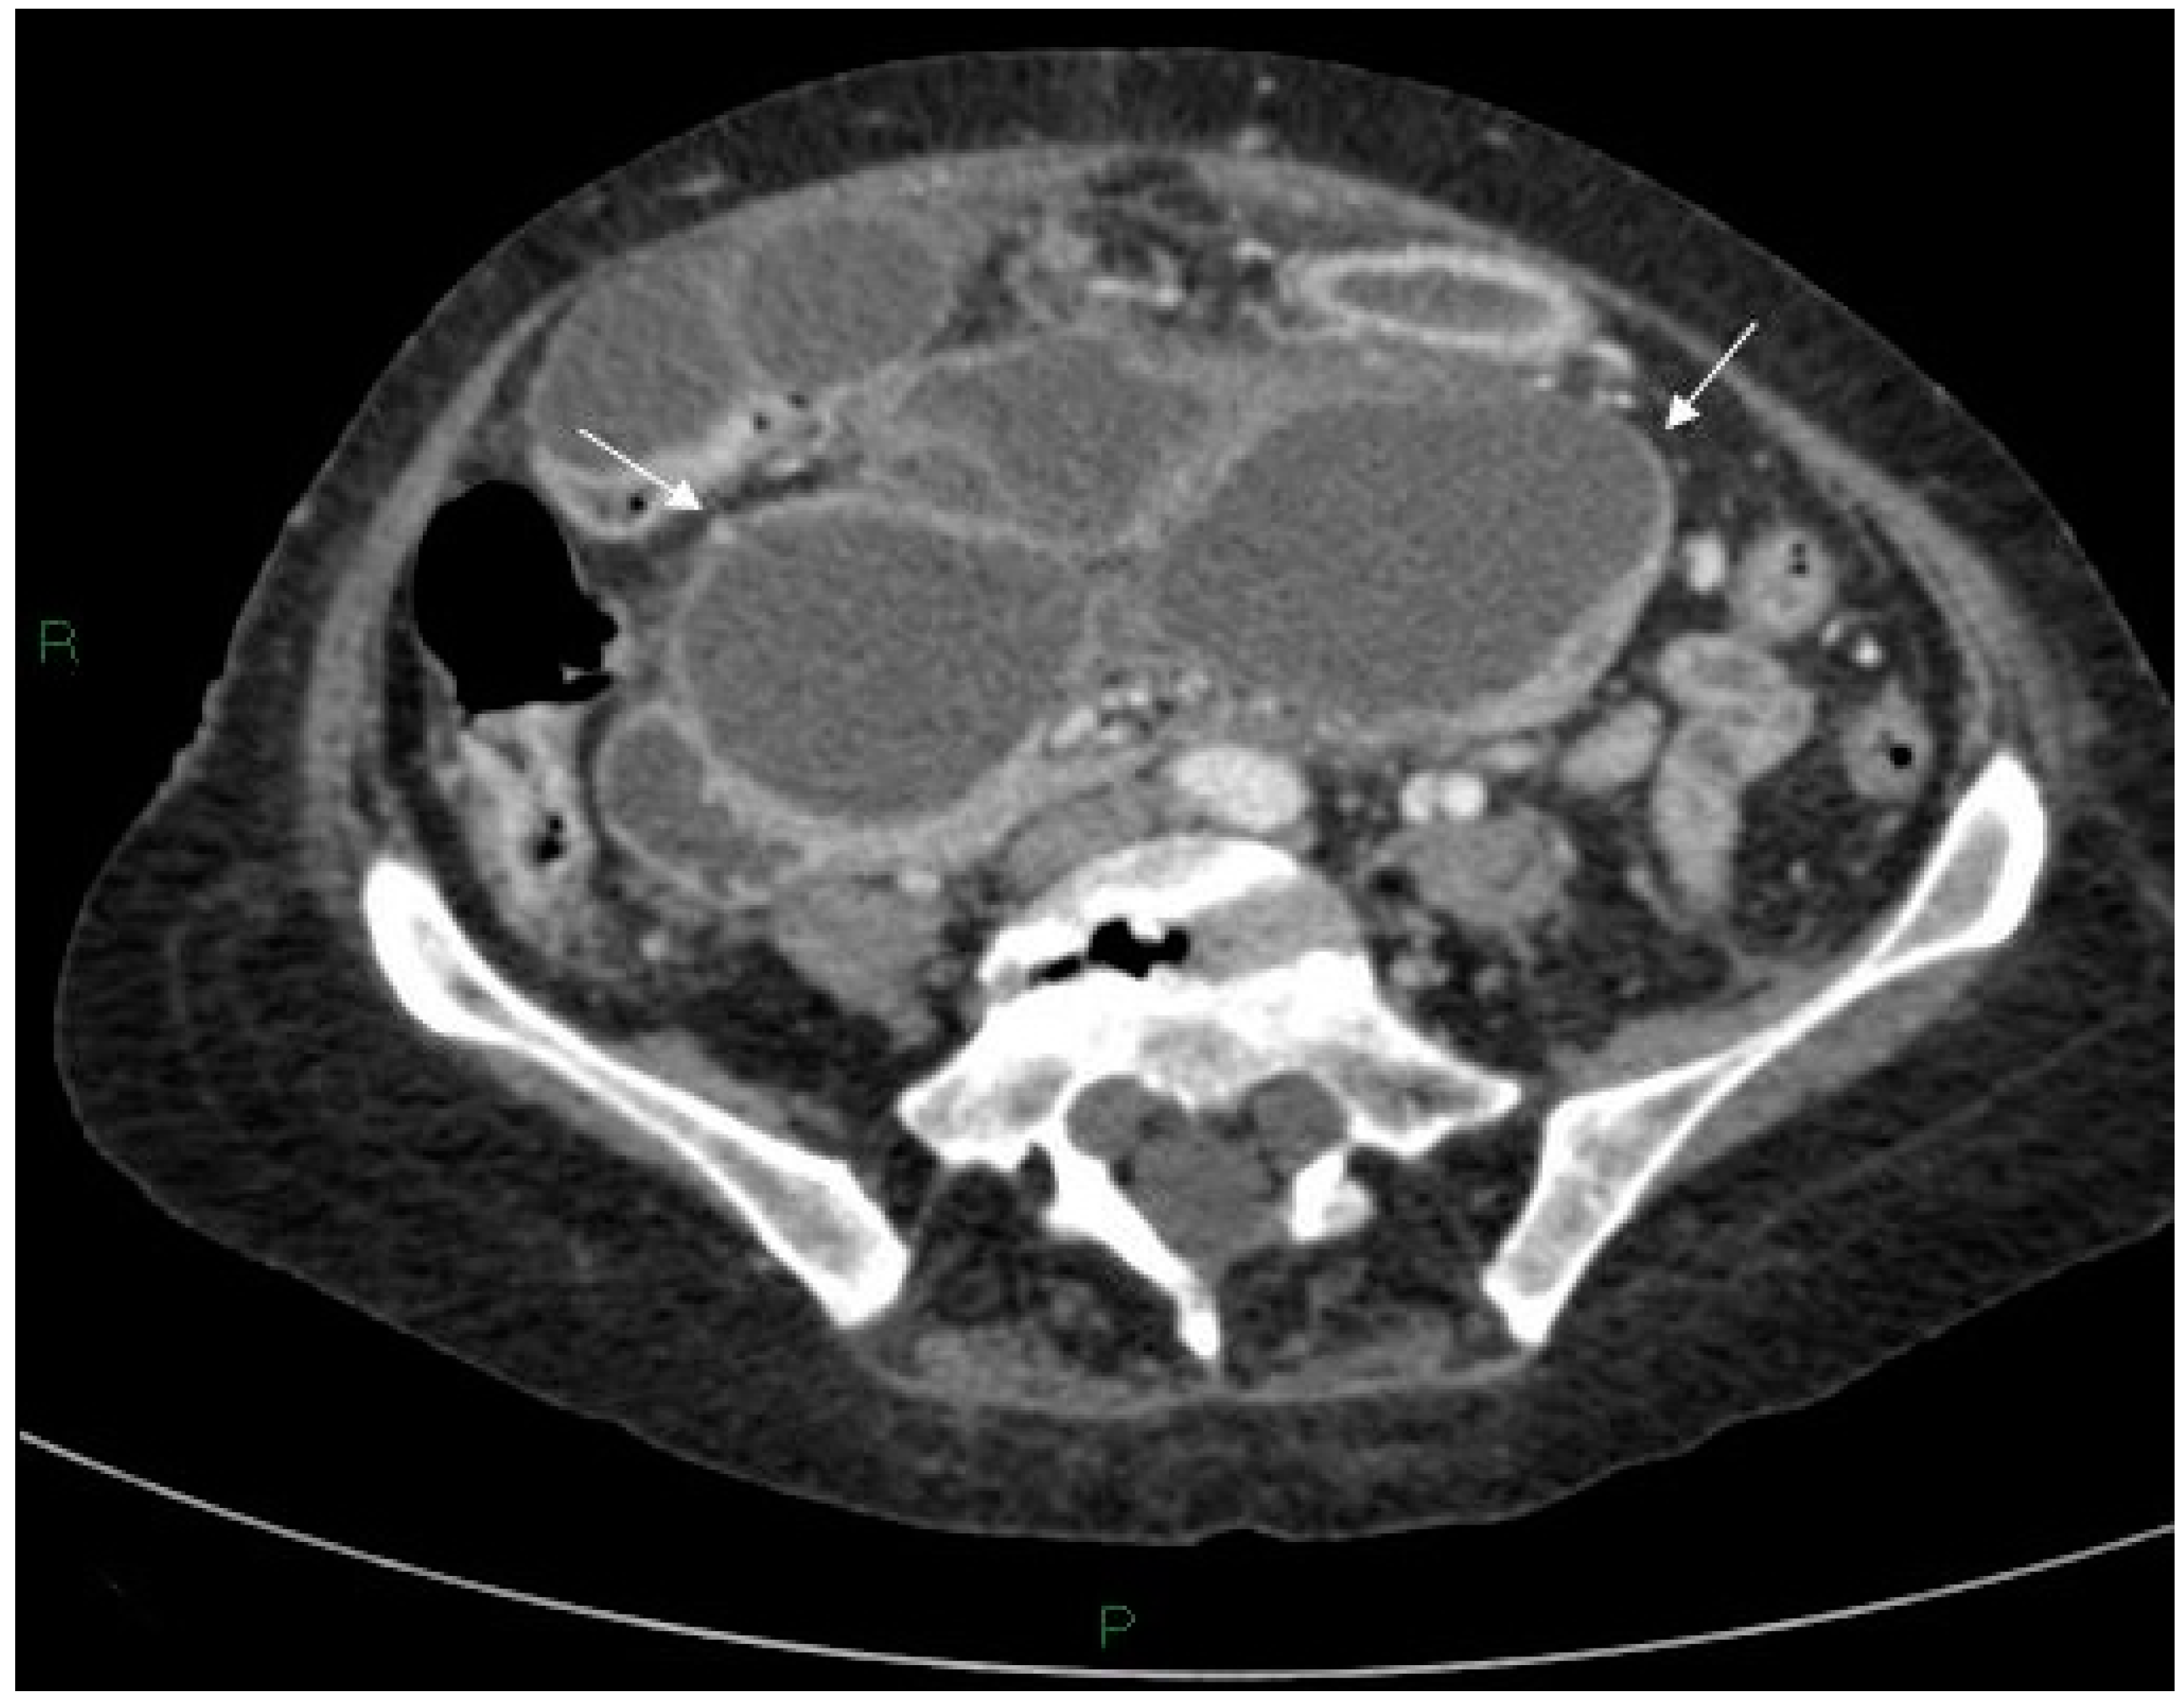

Figure 2.

Axial post-contrast CT scan of the upper abdomen showing the inferior aspect of the cyst with bi-lobed appearance (arrows) in the pelvis.

A 72-year-old female attended for a laparoscopic cholecystectomy on the background of severe gallstone pancreatitis four weeks previously. Examination prior to her operation revealed that she had an upper abdominal mass. The procedure was cancelled, and computed tomography (CT) was performed. This revealed a pseudocyst with three components—a large 16 × 12 cm thin-walled cyst in relation to the head, body and proximal tail of the pancreas, a separate 6 cm cyst in the distal tail, and a 10 × 5 cm cyst in the area of the transverse mesocolon compressing the transverse colon (Figure 1 and Figure 2).